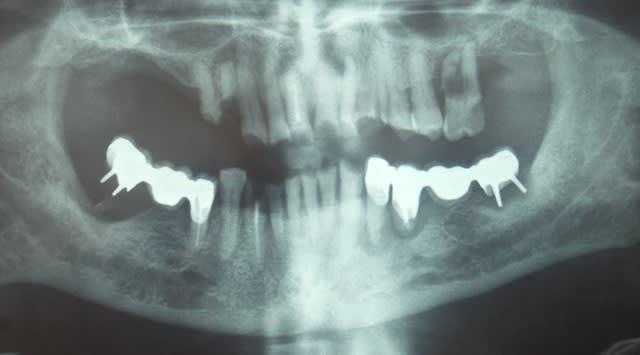

Pour ce cas que j'avais déjà exposé, c'est très intéressant...

Si dés le départ on décide de faire l'endo et couronne, on taille, on ouvre, et a la fin on se dit qu'on a bien fait de faire la couronne, vu qu'il reste pas grand chose. Au passage on perd beaucoup de résistance mécanique de la dent, et on descend toute les limites au niveau gingival ce qui dans le temps expose la limite à une contamination biologique, reprise de carie ...etc...

Ici, je fais l'endo en essayant de garder ce que je peux de la dent...

Ensuite a la fin de l'endo, c'est propre, j'ai un accès étanche, j'en profite pour coller et remonter la limite. C'est le meilleur moment pour le faire, non ? ... Et surement le meilleur moyen d'avoir une étanchéité sur la zone faible de cette dent, sa limite proximale infra gingival.

Onlay Emax. Tout est dans l'émail a part la limite mesiale, le risque de carie est plus faible, le risque de contamination de l'endodonte plus faible aussi...

Mécaniquement ça me parait un meilleur choix que la couronne avec inlay core...